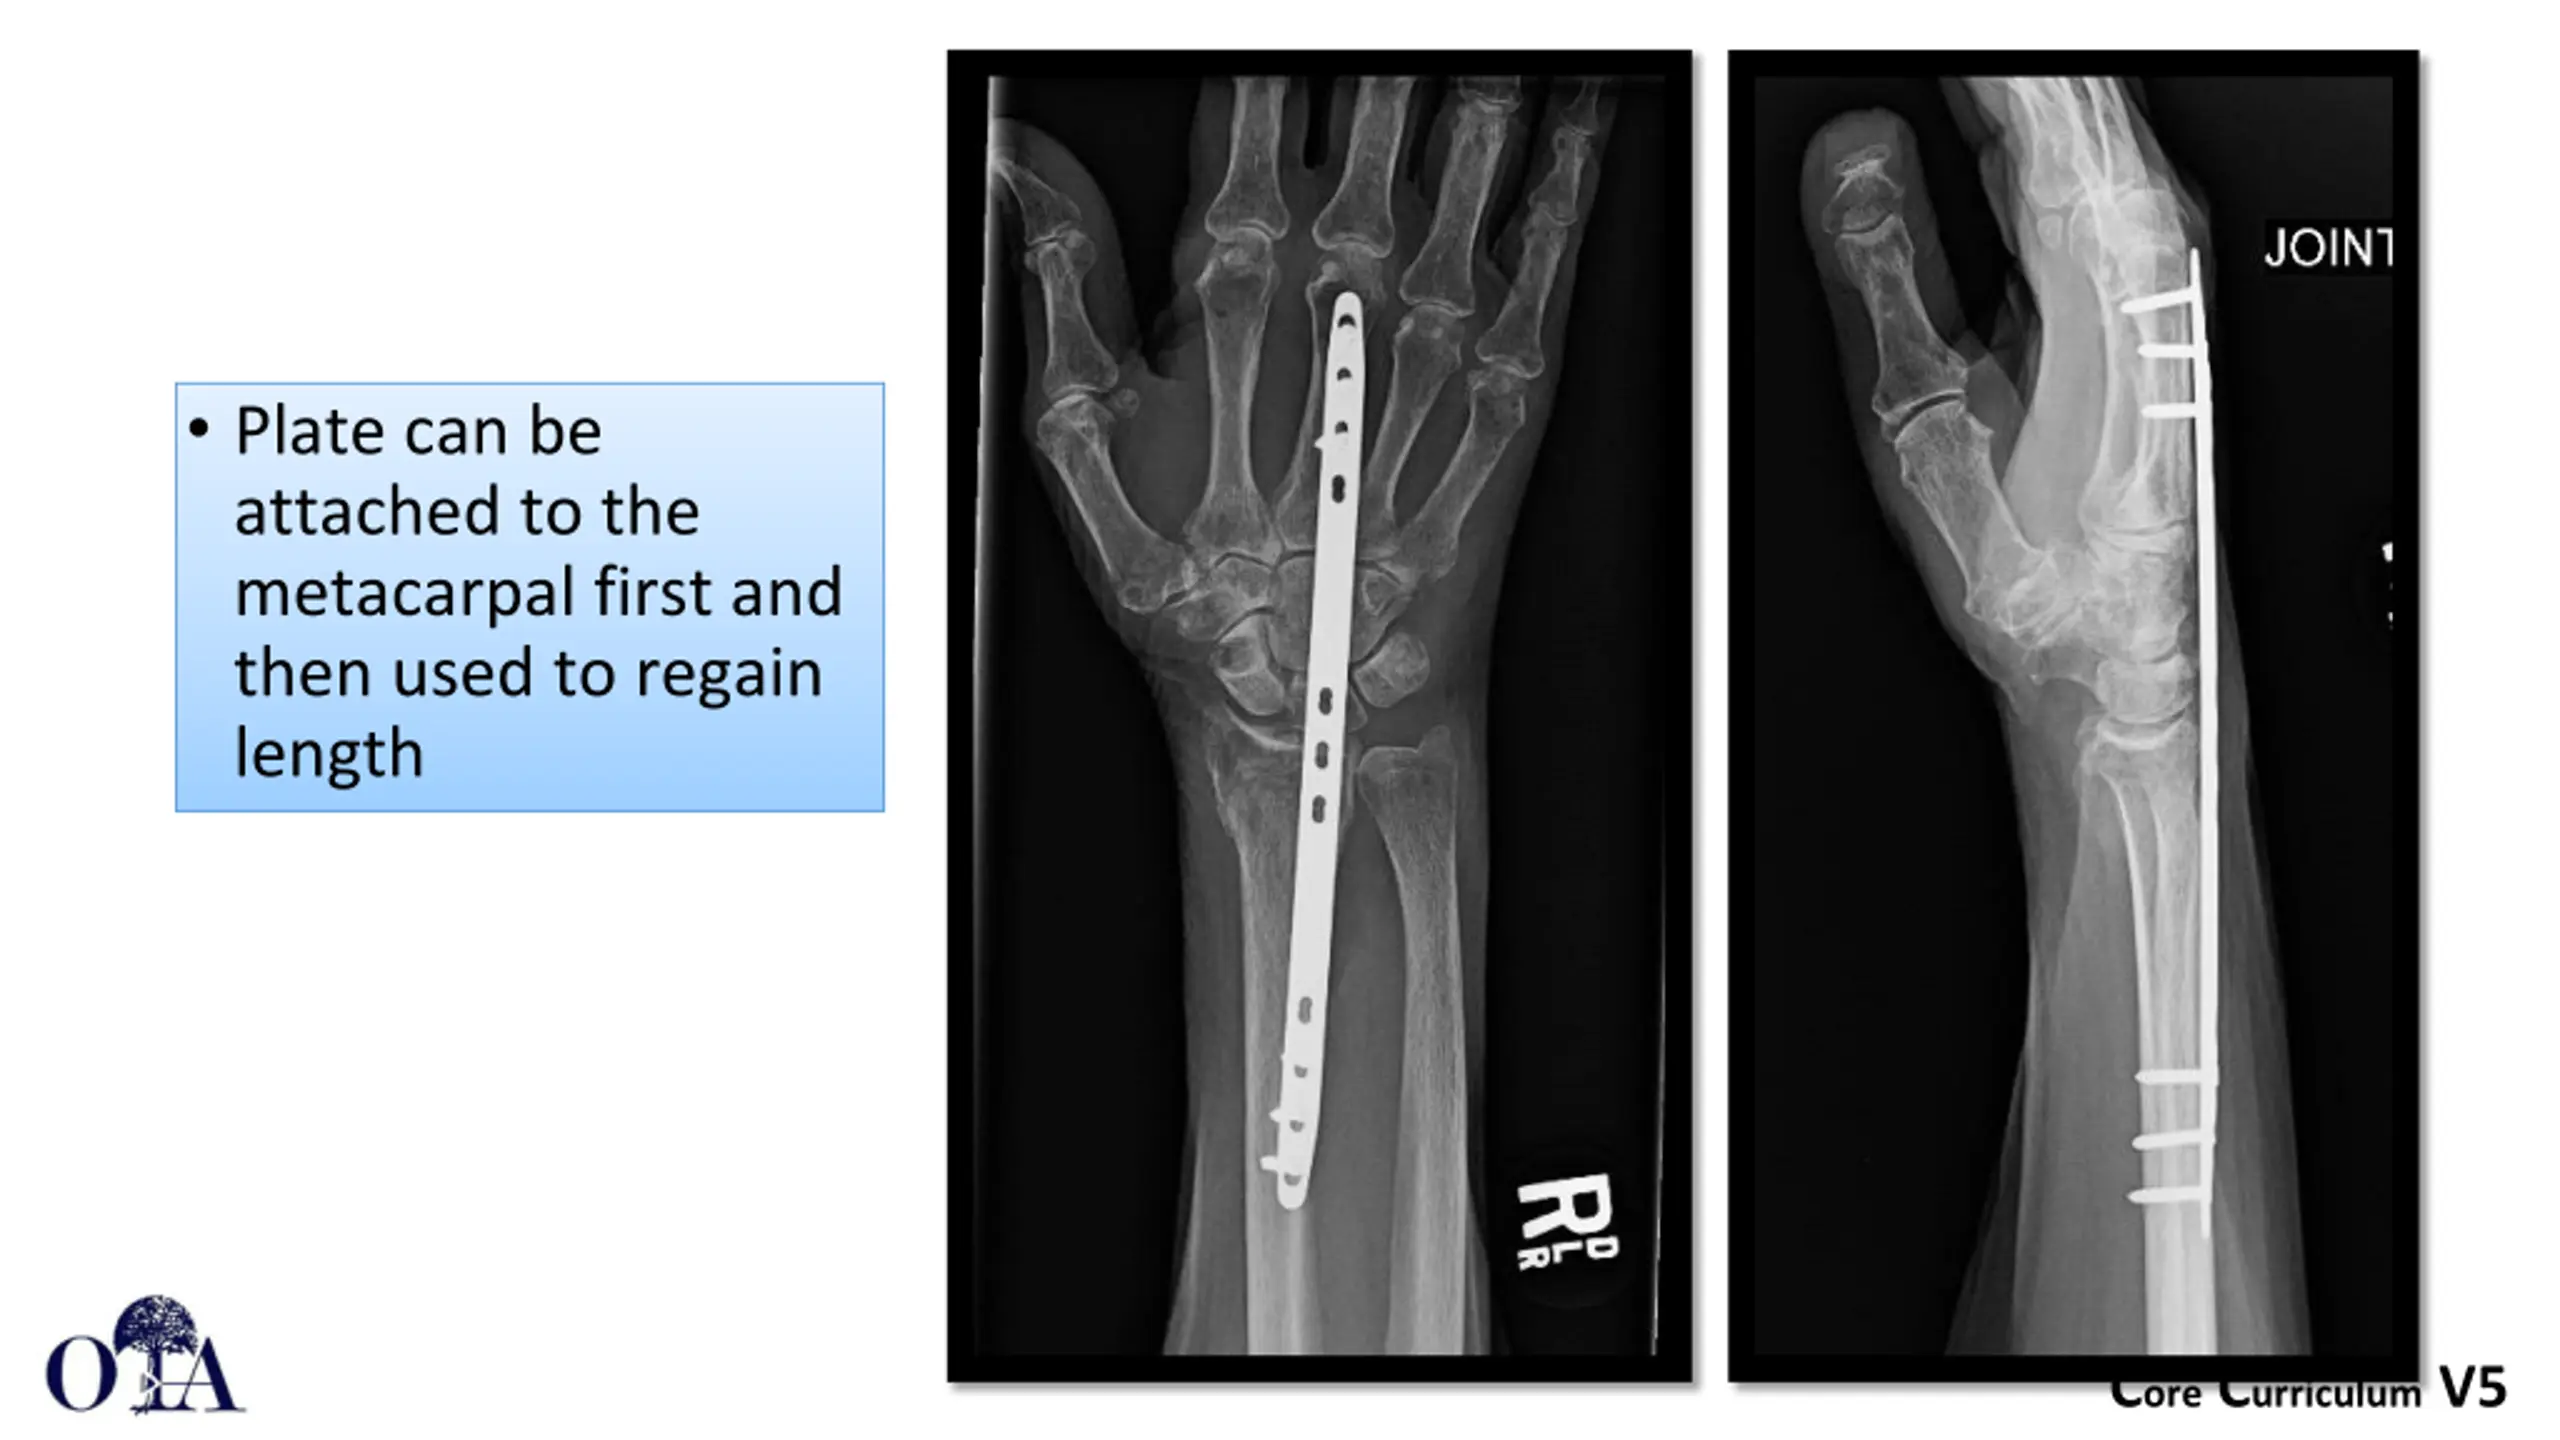

Plate can be attached to the metacarpal first and then used to regain length Core Curriculum V5